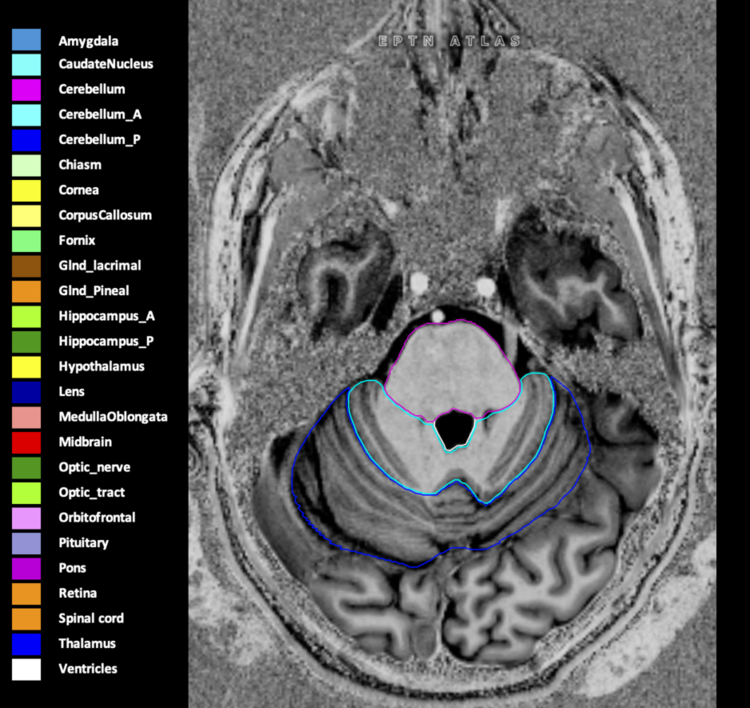

Eekers et al. have published an international neurological atlas for contouring of organs at risk in consensus with the European Particle Therapy Network (EPTN) in 2018 and an update in 2021. The purpose of this consensus atlas is to decrease inter- and intra-observer variability in delineating OARs relevant for neuro-oncology.

Included are all OARs known to be relevant for radiation-induced toxicity in neuro-oncology: brain, brainstem (midbrain, pons, medulla oblongata), chiasm, cerebellum (anterior & posterior), cochlea, cornea, hippocampus (anterior & posterior), hypothalamus, lens, lacrimal gland, optic nerve, pituitary, skin, and vestibular & semicircular canals. To further facilitate research on cognition, vision and radiological changes after irradiation of the brain, potential clinically-relevant OARs are included: amygdala, caudate nucleus, cerebellum (anterior & posterior), corpus callosum, fornix, macula, optic tract, orbitofrontal cortex, periventricular space (PVS), pineal gland, and thalamus.

Three-dimensional delineation of the 25 consensus OARs for neuro-oncology are shown on CT (WW/WL 120/40, 3000/600), 3T MR images, (T1Gd, T2FLAIR 1mm) and 7T MR (MP2RAGE 0.7 mm). All are presented in transversal, sagittal and coronal view.